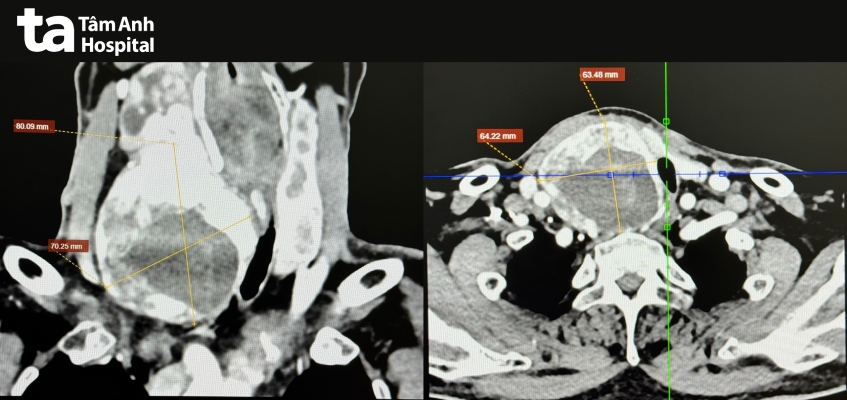

Ông Kỳ, 67 tuổi, có tiền sử tăng huyết áp, rối loạn lipid máu, suy thận mạn giai đoạn 3. ThS.BS.CKI Phạm Ngọc Minh Thủy, khoa Ngoại Tim mạch, Trung tâm Tim mạch, Bệnh viện Đa khoa Tâm Anh TP.HCM, cho biết thùy phải tuyến giáp của ông Kỳ kích thước 68x68x121 mm. Bướu giáp thòng xuống hõm ức, đẩy khí quản, thực quản sang trái, khiến lòng khí quản còn 9 mm (trong khi đường kính bình thường khoảng 20 mm).

Theo ThS.BS Trần Thúc Khang, Phó khoa Ngoại Tim mạch, Trung tâm Tim mạch, đường thở hẹp hơn 55% cho thấy mức độ chèn ép nặng, thực quản nằm sát ngay sau khí quản bị đẩy lệch làm cản trở thức ăn lưu thông xuống dạ dày. Người bệnh có nguy cơ bị khàn tiếng mạn tính, khó thở cấp tính, nhuyễn sụn khí quản (vòng sụn khí quản yếu đi, mất khả năng đàn hồi), ngưng thở khi ngủ, sặc thức ăn vào đường thở… nếu không điều trị kịp thời.